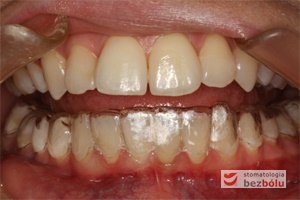

- Wygodne – brak metalowych elementów drażniących błonę śluzową, które są niewygodne i utrudniają higienę. Niedostateczna higiena z kolei prowadzi do demineralizacji i plam wokół zamków jako odwapnienia, a w skrajnych przypadkach mogą być przyczyną próchnicy.